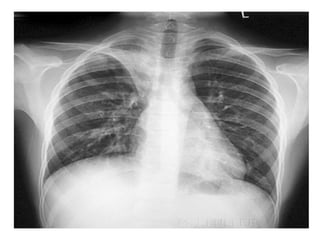

CONSOLIDATION

• Replacement of air in one or more acini by

fluid or solid material

• Smallest unit of consolidated lung is

acinus casts 7mm diameter shadow